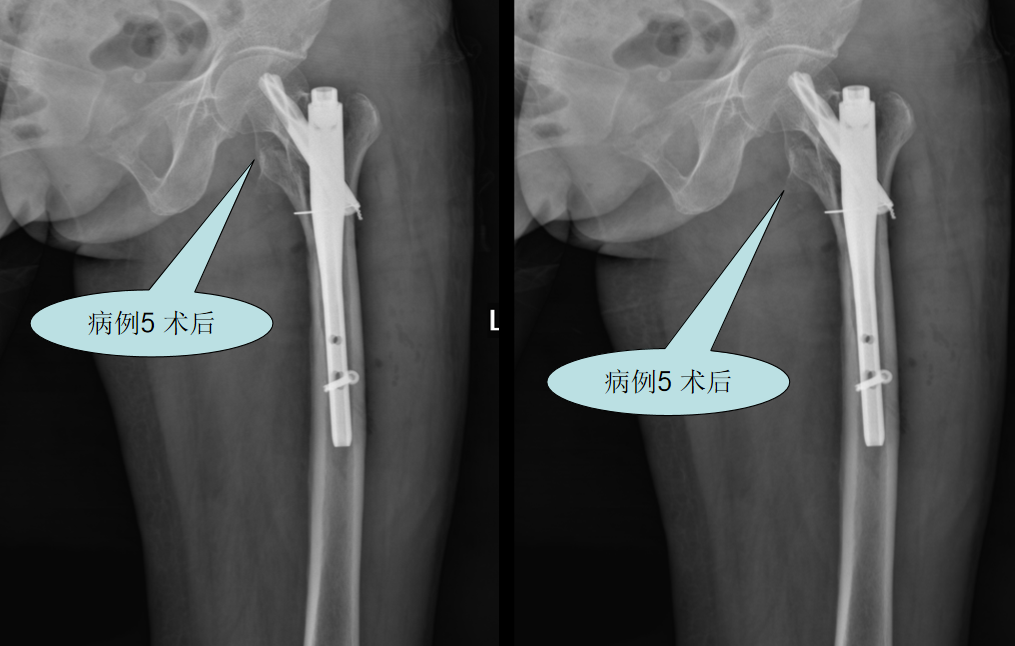

针对老年髋部骨折患者,我院骨科团队主要采取:骨折复位内固定术或髋关节置换手术。

【病例三】